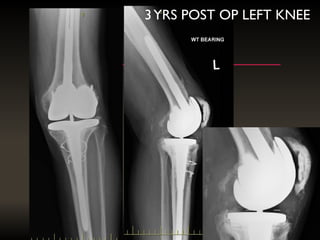

3YRS POST OP LEFT KNEE

3YRS POST OPLEFT KNEE

AN INFECTEDTKR REFERRED AFTER8 MONTHS WITH A SPACER